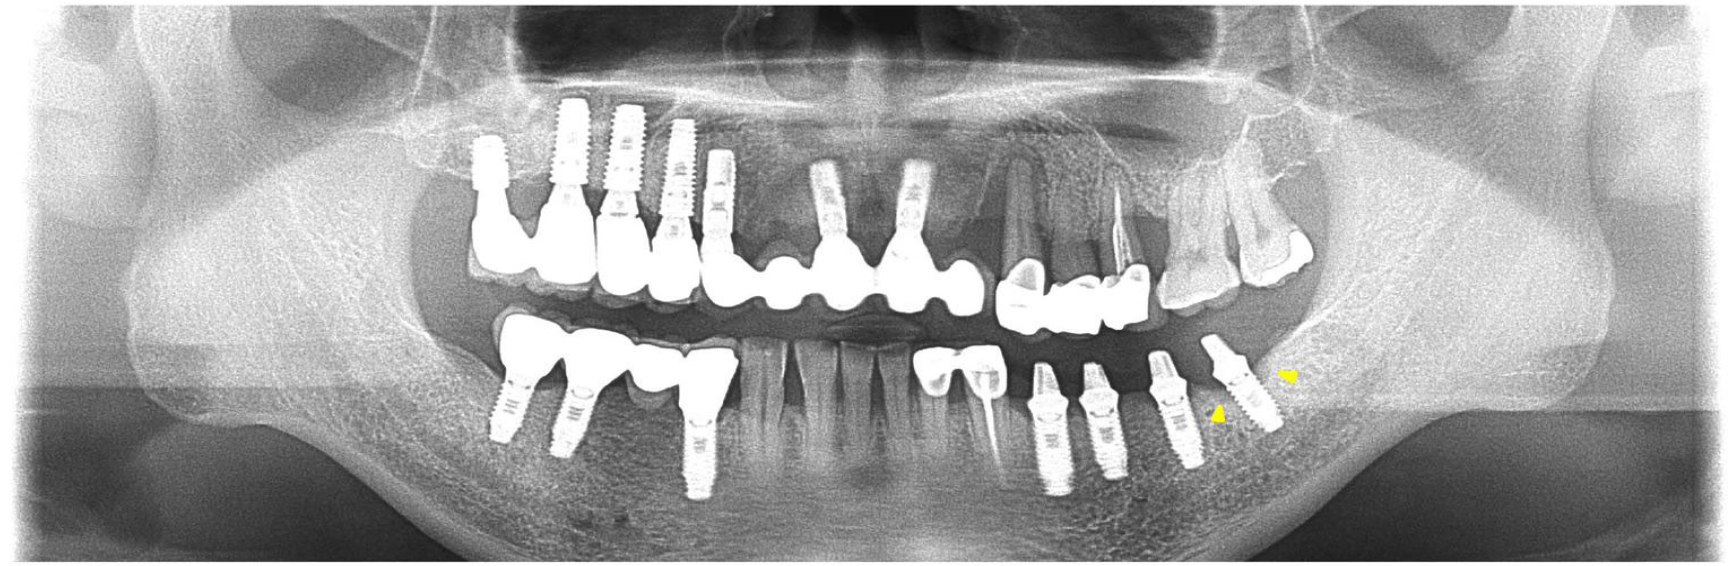

A 66-year-old patient visited the Department of Prosthodontics at the Veterans Health Service Medical Center with a history of placement of multiple implants at another clinic and a complaint of a frequently fractured maxillary anterior prosthesis (Fig. 1). The loss of supporting bone around the implant replacing the mandibular left second molar was observed on a panoramic radiograph. After evaluating the presence of occlusal disharmony, the fabrication of new prostheses was planned for the mandibular right and left posterior regions, as well as the maxillary anterior and right posterior regions. The patient was referred to the Department of Periodontology for pre-prosthetic surgical procedures (crown lengthening of the maxillary left premolars, extraction of the maxillary left canine, and removal of fractured implants from the regions of the maxillary right incisor and canine). Additionally, placement of implants was planned in the maxillary right and left canine regions, while the implant placed in the mandibular left second molar region was evaluated for peri-implant bone loss. This implant was diagnosed with peri-implantitis with deep pockets and bleeding on probing; the implant abutment was in contact with the opposing tooth, and prosthetic restorations were not retained because of recurrent fractures and chipping of porcelain (Figs. 1, 2A, 2B, 2C).

A 65-year-old patient presented with mobility of the bilateral maxillary posterior teeth. Clinical examination revealed alveolar bone resorption and impaired masticatory function. The mandibular right first molar and left second molar implants were diagnosed with peri-implantitis as funnel-shaped crestal bone loss was observed around the implants on examination of clinical parameters and radiographs (Fig. 4A). These implants received a non-surgical treatment similar to that administered in Case 1. After a full-mouth rehabilitation was planned for restoring occlusal harmony, the implants were placed in the maxillary right and left posterior edentulous regions and the mandibular anterior region, while the prostheses supported by the mandibular posterior implants on both sides were modified without fabrication of new prostheses. Recovery of the marginal bone was observed on radiographs, and improvements in clinical periodontal parameters were documented at the 6-year follow-up (Fig. 4B).

The following clinical and radiographic parameters, as previously reported,8 were assessed at baseline and follow-up in both cases via a comparison of the clinical and radiographic findings: modified plaque index, modified sulcus bleeding index, probing depth, and distance from the implant shoulder to first5bone-to-implant contact (in mm). Additionally, we evaluated peri-implant bone recovery after treatment by superimposing cone-beam computed tomography images at baseline and follow-up. Additional manual correction was performed for the best-matched cuts. Panoramic radiographs were also updated at follow-up and compared with those obtained at baseline. Oral hygiene was well maintained, and both patients showed improvements in clinical and radiographic parameters (Table 1, Fig. 5), thereby demonstrating marginal bone recovery around the implants after non-surgical therapy and occlusal correction.